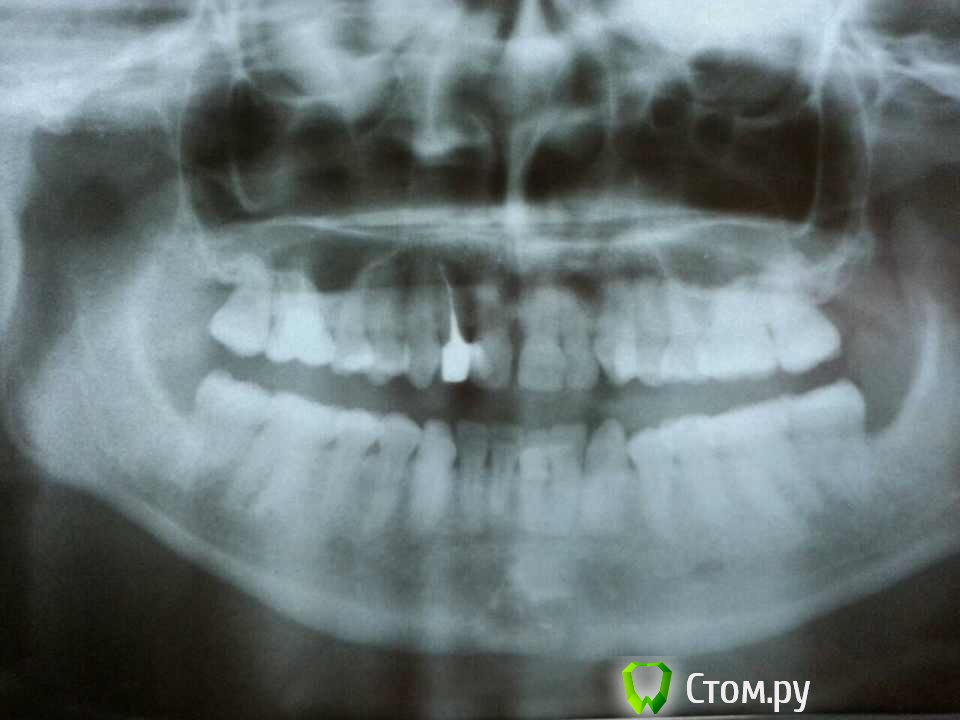

Ярка Опубликовано 17 февраля, 2014 Поделиться Опубликовано 17 февраля, 2014 Здравствуйте, у меня есть проблема с правым нижним шестым зубом. Уже года 3 он у меня периодически очень слабо ноет, чувствителен к холоду, между шестеркой и пятеркой часто воспаляется десна. Я ходила с этим зубом к нескольким стоматологам, показываю его примерно раз в 4-6 месяцев, но каждый раз во всех клиниках у меня ничего не находят, говоря, что с зубом все в полном порядке. Сегодня снова показывала его, снова делала рентгент и снова ничего не нашли, а периодическое нытье объясняют тем, что зубы плотно прижимаются друг к другу в этом месте. Может быть вы что-то сможете увидеть по этому снимку. Ссылка на комментарий

diesel87 Опубликовано 17 февраля, 2014 Поделиться Опубликовано 17 февраля, 2014 Здравствуйте, по снимку самое интересное не видно, верхушки корней. Видна только пломба близко к полости с нервами, а помимо того что он периодически ноет что еще беспокоит? Реакция на холодное или сладкое, боль при накусывании или самопроизвольные боли? Еще возможно есть карман между 5 и 6 зубами, есть не приятный запах? Ссылка на комментарий

Ярка Опубликовано 18 февраля, 2014 Автор Поделиться Опубликовано 18 февраля, 2014 выложите панорамный снимок (ОПТГ) сегодня появилась возможность сделать панорманый снимок Ссылка на комментарий